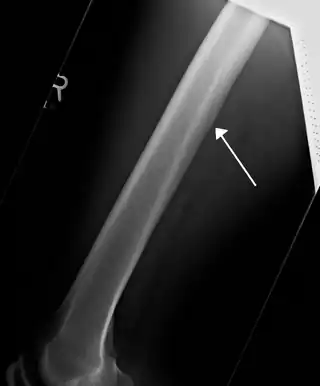

![]() Radiografía mostrando una arteria nutricia irrigando el fémur. | ||

Se conoce como arteria nutricia (TA: arteria nutriens) a cualquier arteria que irriga la médula ósea de un hueso largo.[1]